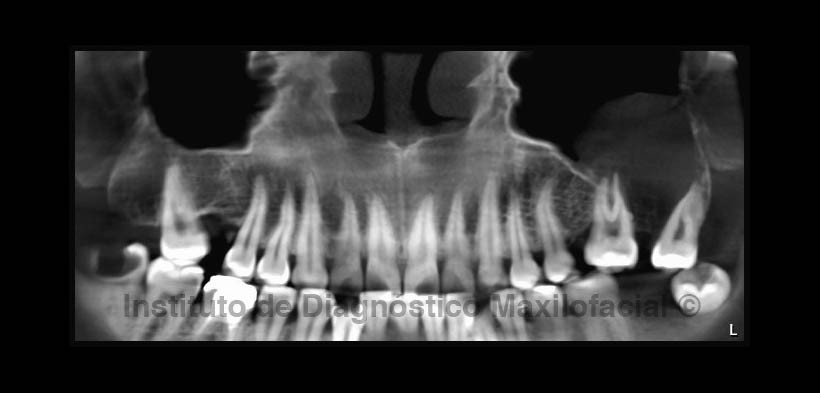

A la radiografía panorámica (Fig.1) se observa la presencia de una imagen radiopaca de densidad de tejido blando proyectada sobre el proceso alveolar del maxilar superior izquierdo y la apófisis cigomática, comprometiendo la pared basal del seno maxilar, así como la reabsorción ósea a nivel del tercio apical de la pieza 2.6 y se extiende hacia el proceso alveolar correspondiente a las piezas 2.7 y 2.8; produciendo la divergencia radicular de esta última.

También se observa la ausencia de las piezas 1.6, 1.8 y 3.7; la pieza 4.6 con restauración coronaria con falta de sellado, obturación parcial de conductos y ensanchamiento del espacio para el ligamento periodontal a nivel apical con aumento de la densidad ósea circundante sugerente de osteítis condensante; además de la pieza 3.8 con orientación bucolingual e impactada sobre el borde anterior de la rama ascendente, con una imagen radiolúcida por distal de la corona, a descartar pericoronaritis; y la pieza 4.8 con una lesión cariosa amplia y profunda con probable compromiso pulpar.